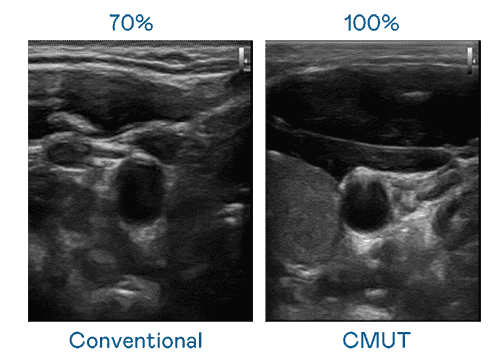

CMUT 技术是一种用电容式微机电元件来产生超音波讯号的技术。。。与传统 PZT 压电式技术相比,,CMUT 频宽增加 30%,,,,更宽频的超音波讯号让影像解析度大幅提升,,,,是实现高影像品质医疗超音波扫描、、促进精准医疗发展的关键技术。。。。

大频宽带来超清晰影像

超音波影像的解析度高低,,首先取决于探头能发出的讯号频宽。。至成国际 CMUT 可提供高清晰的超音波讯号,,,,提供高频宽、、高灵敏度、、、影像纹理细节更高的超音波影像,,协助医护人员缩短影像判读时间及利用精准的医疗影像进行诊断。。